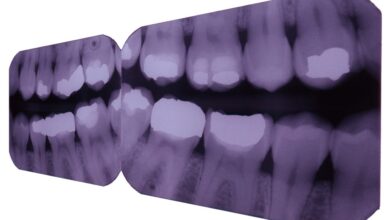

Диагностика рака кожи Диагностика рака кожи играет важную роль в своевременном выявлении заболевания и повышении шансов на успешное лечение. Различные…